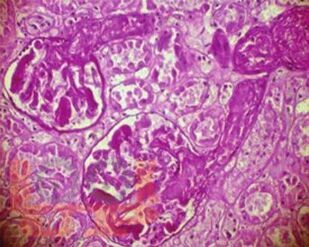

В монографии обобщены результаты исследований авторов и современные литературные данные, посвященные тромботической микроангиопатии у пациентов, находящихся в листе ожидания трансплантации почки, и у реципиентов ренального трансплантата. Большое внимание уделяется патогенетическим механизмам, классификации, проблемам профилактики, ранней диагностики и лечения тромботической микроангиопатии после трансплантации почки, а также влиянию данного осложнения на ближайшие и отдаленные результаты трансплантации.